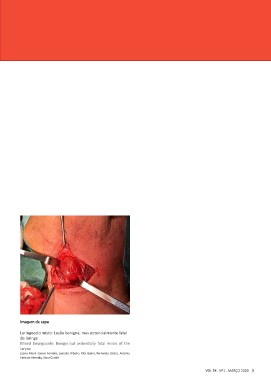

Imagem de capa

Laringocelo misto: Lesão benigna, mas potencialmente fatal

da laringe

Mixed laryngocele: Benign but potentially fatal lesion of the

larynx